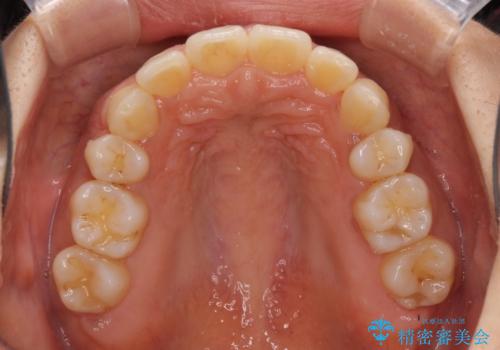

- 以前矯正治療をされていましたが、後戻りが起きたことを気にして来院された患者様です。

全顎的に認められた叢生を改善するため、インビザラインにて治療を行うこととしました。

前歯の叢生の改善を目的として、IPR(歯と歯の間を削る)と歯列全体の後方移動によって歯並びを整えることとしました。

毎日22時間の装着時間を守ってくださいましたが、ハイペースにマウスピースを交換することなく、慎重に治療を進めてくださったので、治療期間はやや長くなりました。

臼歯部も含め、叢生が綺麗に改善され、患者様には大変満足していただきました。